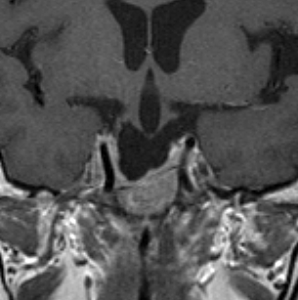

左は下垂体腺腫(緑の腫瘍)が内頚動脈に挟まれていることを示しています。

中央は手術前の下垂体腺腫で,視神経も正常下垂体も位置はわかりません。

右は手術翌日の画像です。黄色の矢印の先が残した正常下垂体組織です。桃色の矢印の先に視神経(視交叉)がはっきり見えています。術後の一時的な尿崩症がありました。クモ膜が残っているので髄液漏は生じませんでした。でも正常下垂体組織(黄色矢印)も視交叉も腫瘍に圧迫されてペラペラになっていますから,いつもうまく行くとは限りません。